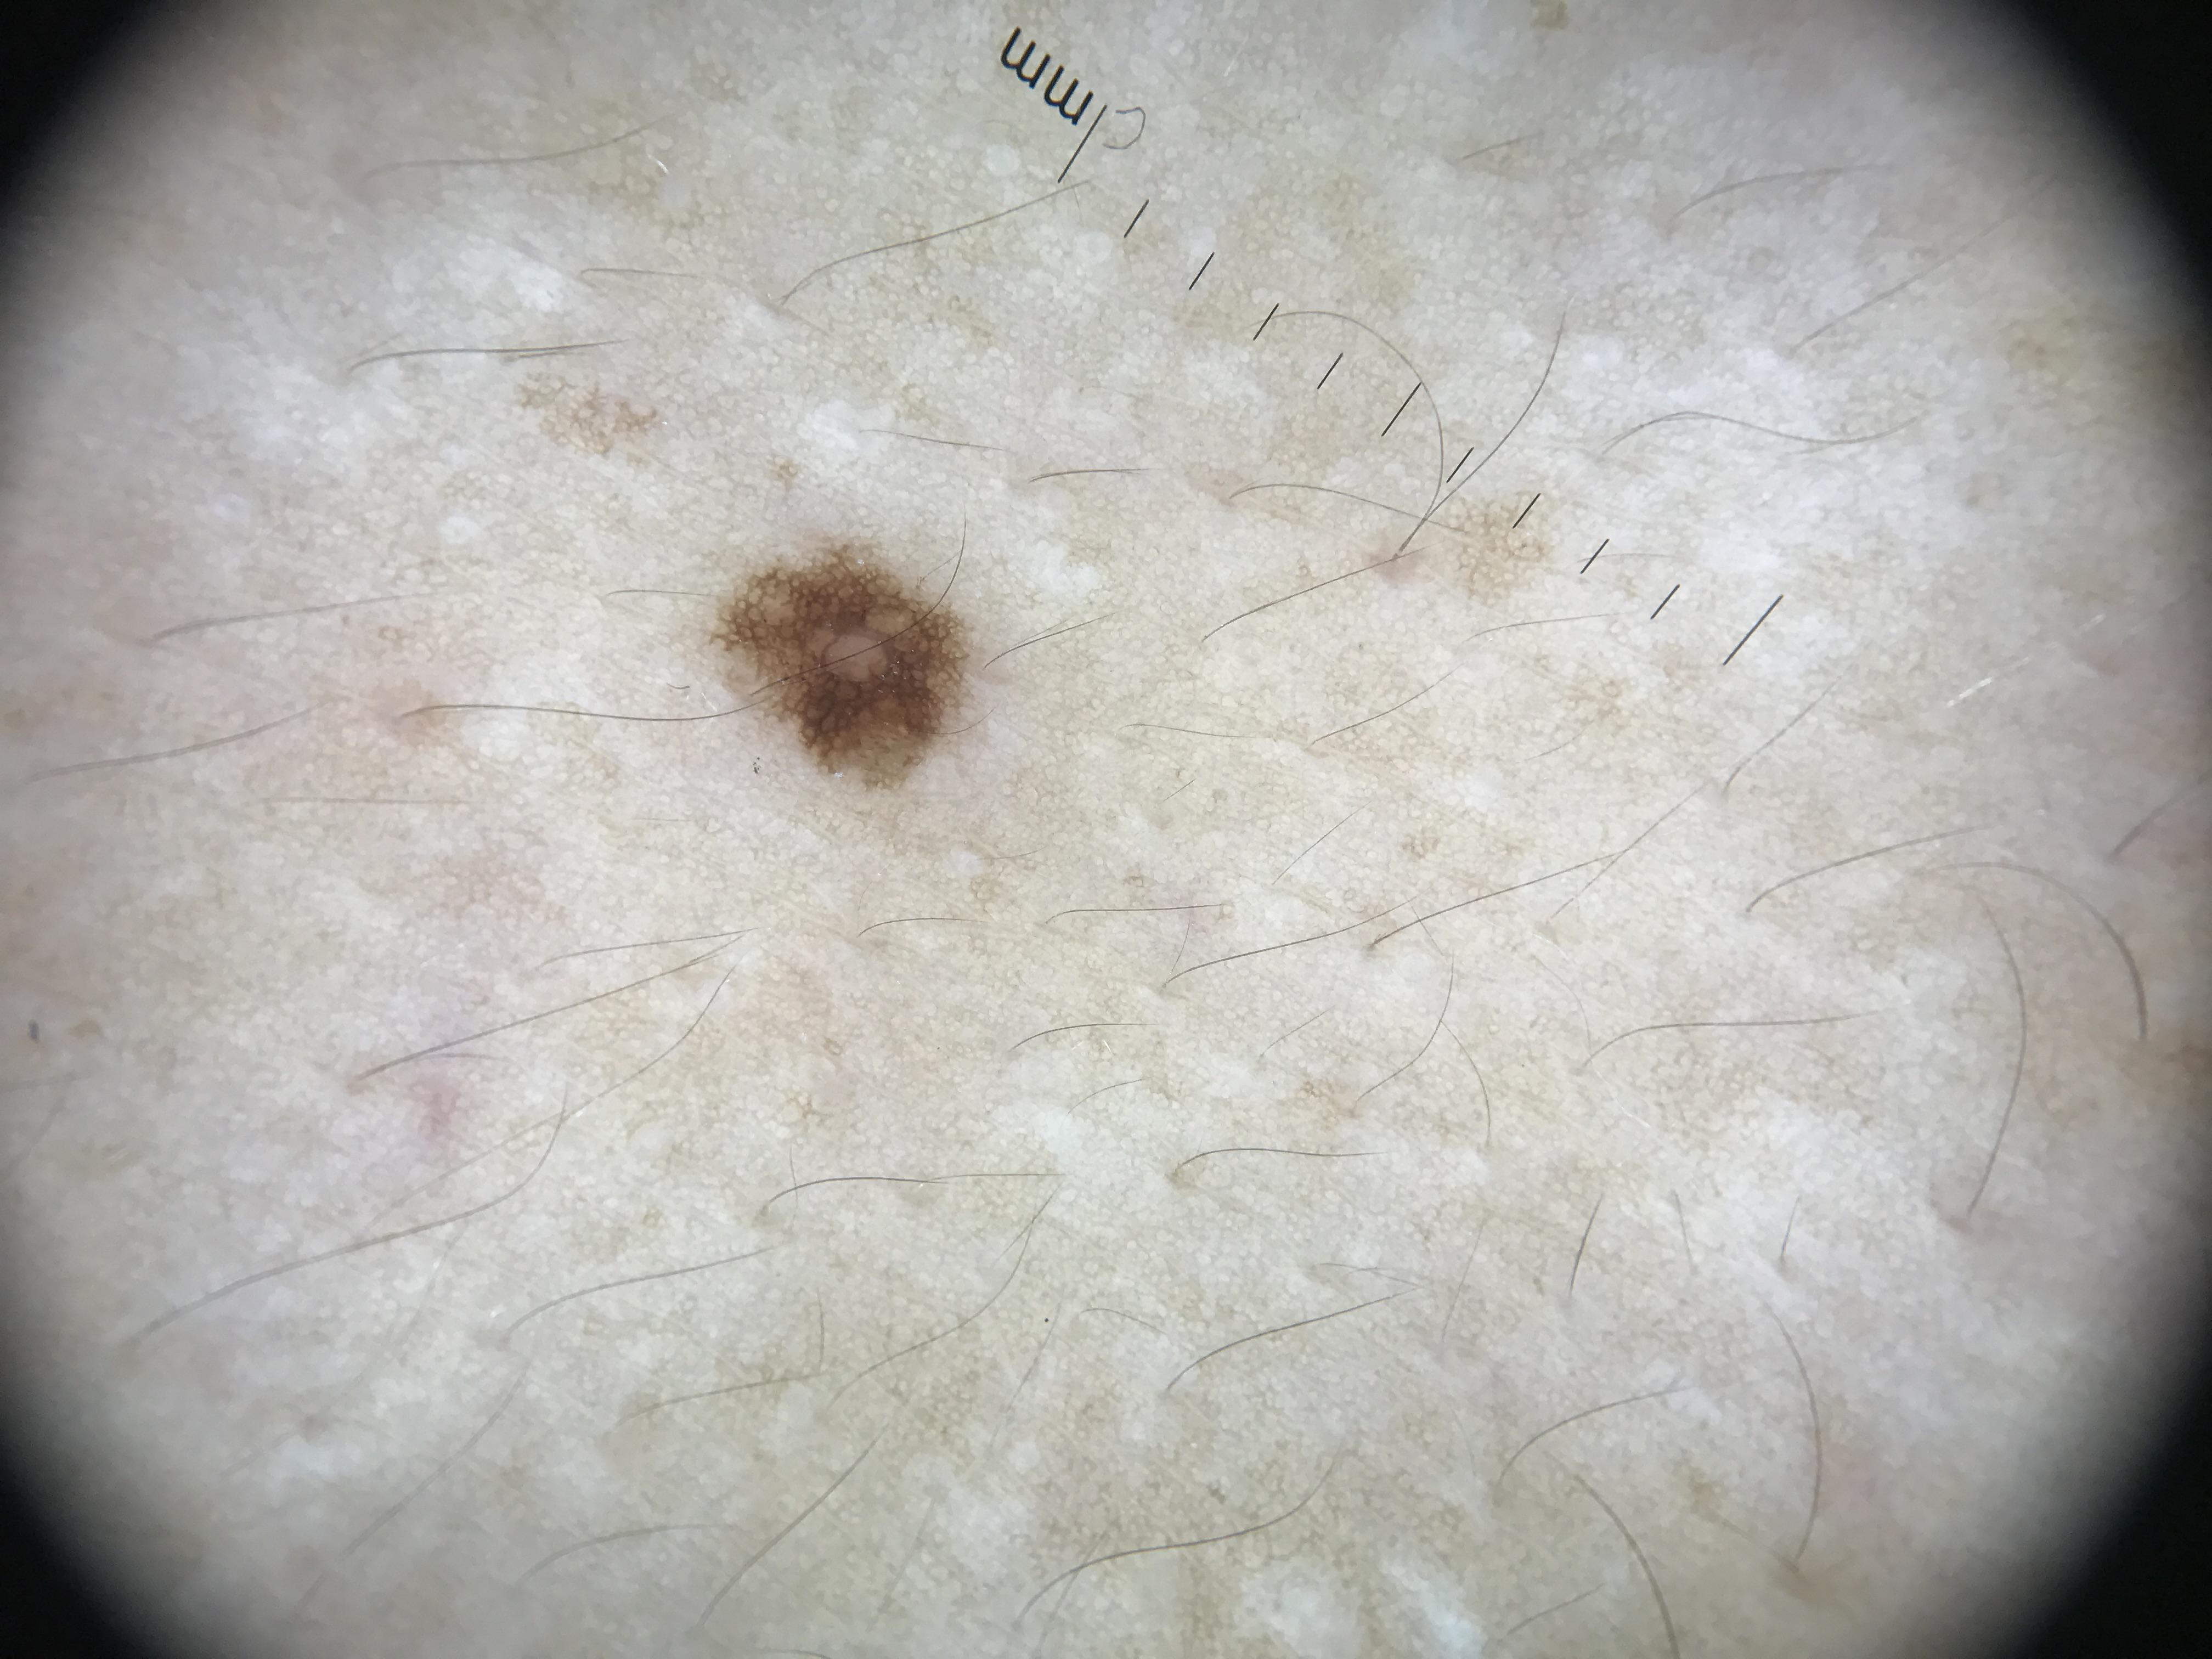

ISIC_0820122

4032 x 3024

Imperial College London

diagnosis_1

Benign

diagnosis_2

Benign melanocytic proliferations

diagnosis_3

Nevus

diagnosis_4

Nevus, NOS, Junctional

image_type

dermoscopic

melanocytic

True